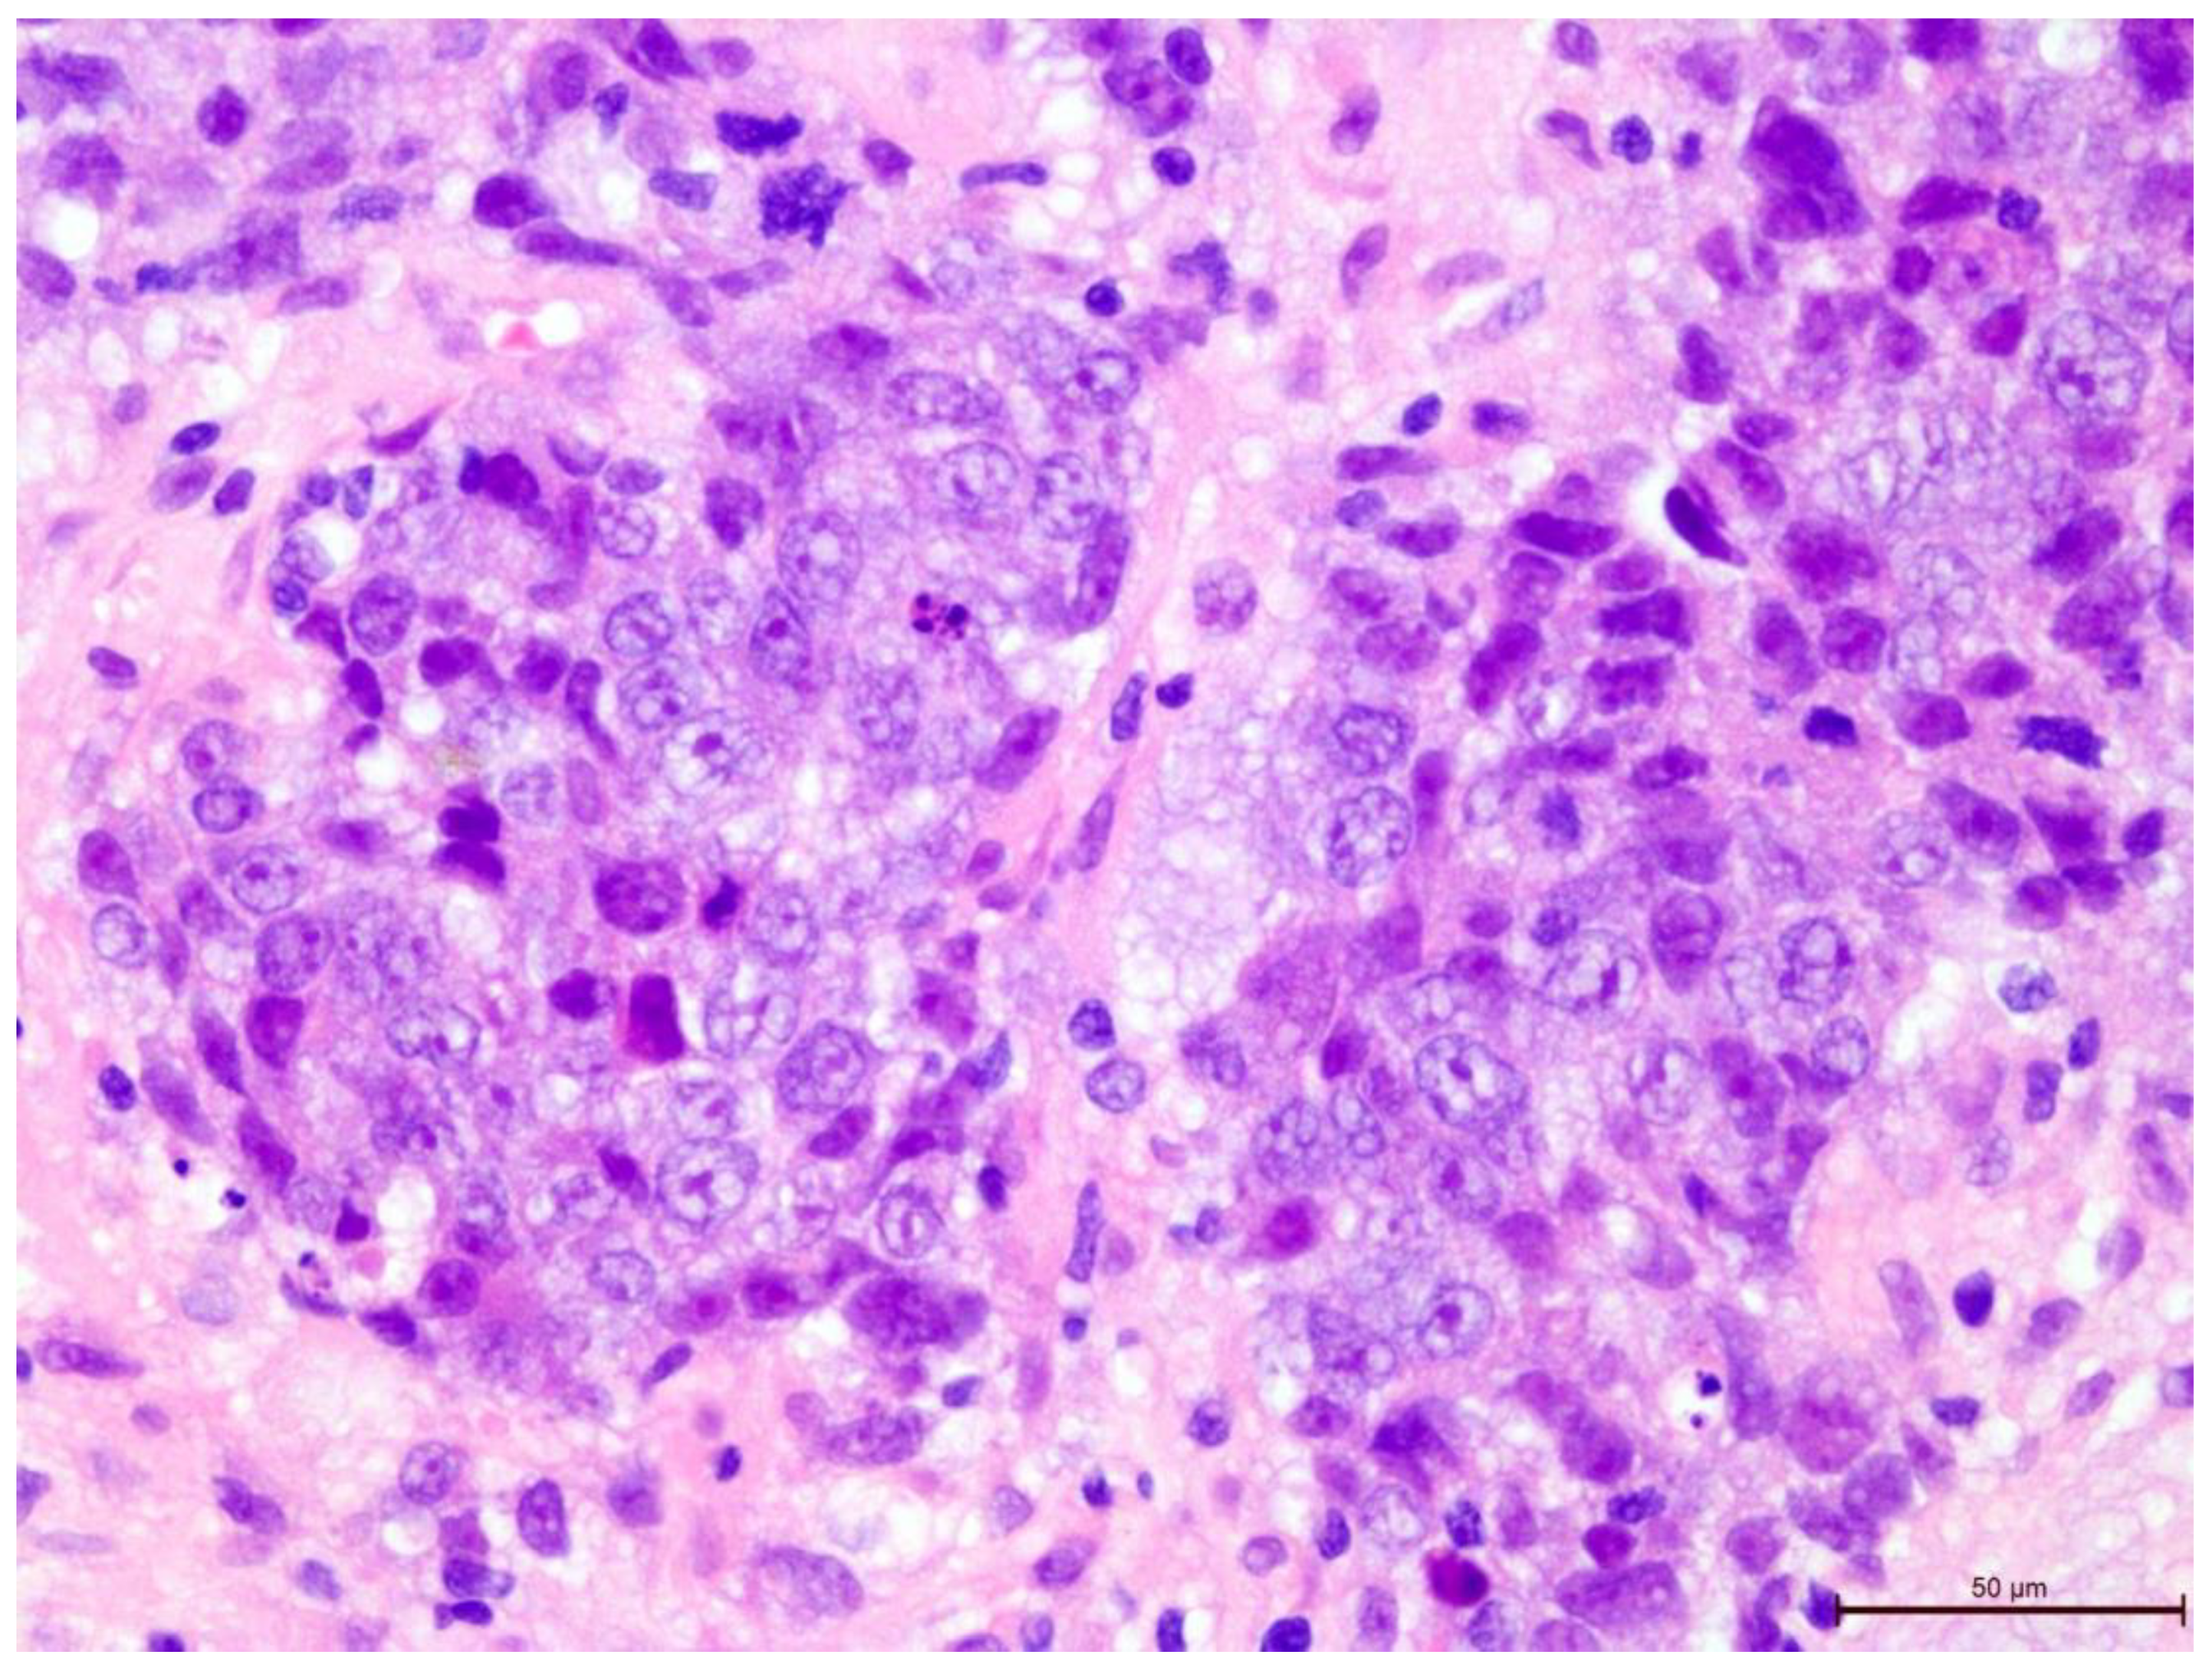

The T-lymphocyte infiltration in the tumor stroma was assessed according to the recommendations of the International Working Group on Immuno-Oncology of Breast Cancer Biomarkers (Figure 2, Figure 3, Figure 4, Figure 5, Figure 6 and Figure 7). The results are reported as the percentage of lymphocytes in the tumor stroma.

Figure 2. Invasive breast cancer with 70% T-lymphocyte infiltration in the tumor stroma, H&E staining, 630×.

Preprints 109573 g002

Figure 3. Invasive breast cancer with 70% T-lymphocyte infiltration in the tumor stroma, H&E staining, 400×.

Preprints 109573 g003